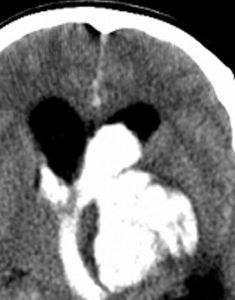

1、CT檢查

臨床疑診腦出血時首選CT檢查,可顯示圓形或卵圓形均勻高密度血腫,邊界清楚,並可確定血腫部位、大小、形態,以及是否破入腦室、血腫周圍水腫帶和占位效應等;如腦室大量積血可見高密度鑄型,腦室擴張。1周后血腫周圍可見環形增強,血腫吸收後變為低密度或囊性變。CT動態觀察可發現進展型腦出血。